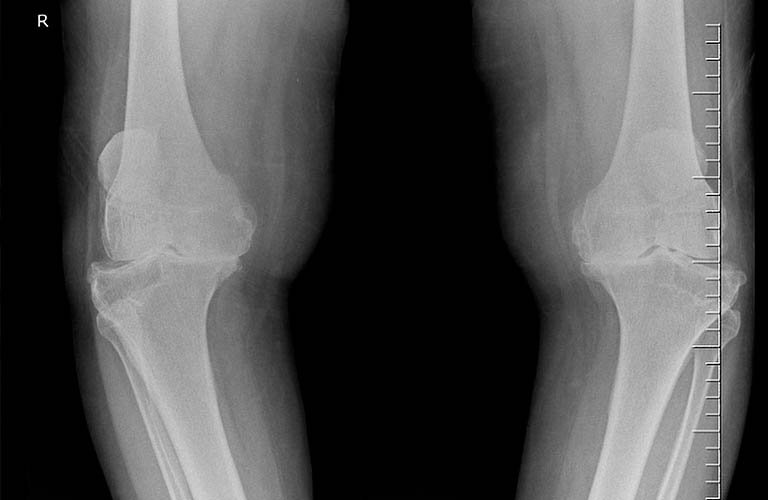

- X quang khớp gối: Thường gặp 3 dấu hiệu cơ bản:

- Hẹp khe khớp gối: Khe khớp có bờ không đều .

- Đặc xương dưới sụn

- Mọc gai xương: Gai xương hình dạng thô và đậm đặc thường gặp ở phần tiếp giáp giữa xương, sụn khớp và màng hoạt dịch.